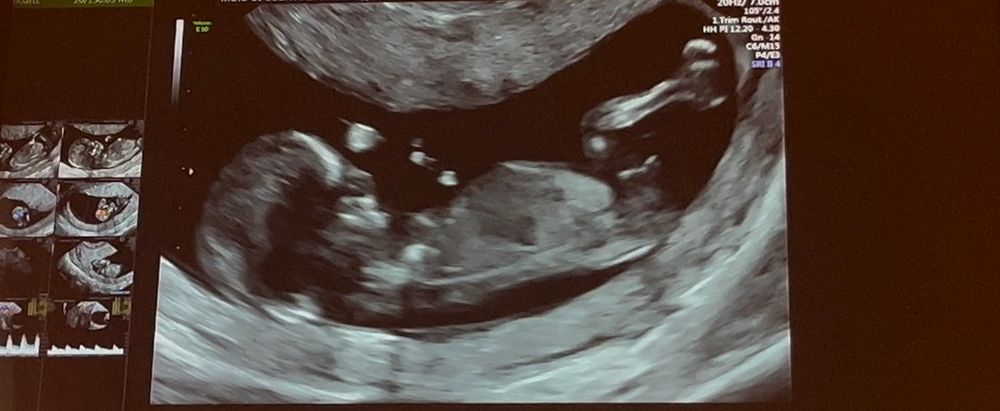

Узи 11.6 недель. Есть тут специалисты по определению пола?😅

УЗИ, КТГ, доплерВот и настал день 1 скрининга. С малышом ттт все в порядке, гематомы большем нет, срок день в день по УЗИ. Была в бесплатной жк, соответственно, про пол речи даже не было. Хорошо хоть дали видео кусочек снять.

Так вот просматривая видео в очередной раз, решила записаться в эксперты, найти половой бугорок. Девочки, я правильно нашла или это нога?))))) И если да, то на кого похоже?

Ну если сравнивать с моим похожим фото, то у вас все по другому. Думаю мальчик

Александра, мне кажется, это фрагмент пуповины, но я не врач)

А я так понимаю девочка) у мальчика на пупок же должен бугорок смотреть!